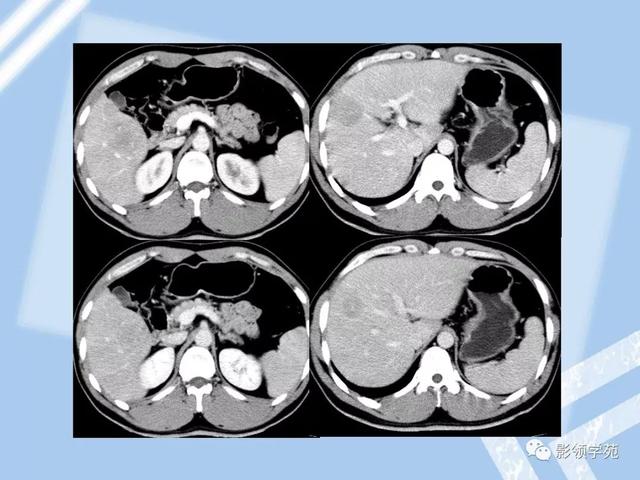

22种肝脏少见及不典型肿瘤的影像表现

图片尺寸640x480